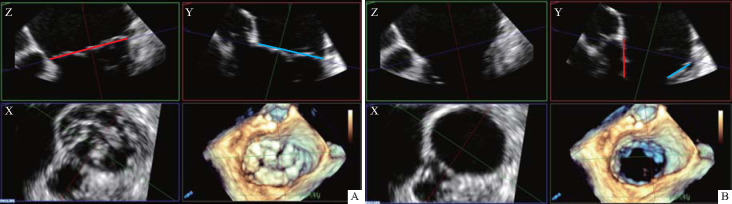

Methods: The study group comprised of thirty-two adult patients with atrial septal defect who underwent thoracoscopic repair surgery at the First Affiliated Hospital of the Air Force Medical University from March to September 2022. Two-dimensional and real-time three-dimensional transesophageal ultrasonography of the mitral valve were performed after anesthesia. The parameters of the mitral valve structure at the late diastolic and late systolic stages were recorded, including anteroposterior and left-right annular diameters, anterior and posterior valves lengths, the vertical distance from the coaptation point of leaflet zone 2 during systole to the annular plane (mitral valve coaptation depth) and mitral valve coaptation length. Data from 32 patients with normal intracardiac structure and no mitral valve regurgitation (control group) were also collected and compared with those of the study group. Concurrent mitral valvoplasty was performed during the atrial septal defect repair surgery for 7 patients with significant mitral valve structural abnormalities and 2 patients with significantly increased mitral regurgitation after cardiac resuscitation. The study group was followed up with transthoracic echocardiography for 2 years postoperatively.

Results: In the study group, 26 (81.3%) patients had varying degrees of mitral valve morphological abnormalities. Among them, 10 (31.3%) patients had short mitral valve coaptation length or depth, 12 (37.5%) patients had closure point malposition, and 4 (12.5%) patients had different bulge of anterior and posterior leaflets. Compared with the control group, the study group had significantly smaller systolic and diastolic mitral left-right annular diameter, mitral posterior valves lengths, mitral coaptation length or depth (all P<0.05), a higher pulmonary systemic flow ratio (P<0.01), and a lower maximum blood flow velocity across the mitral valve (P<0.05). After 2 years of follow-up, among the 9 patients who underwent concurrent mitral valvoplasty, the mitral valve maintained no or little regurgitation, and the average mitral valve pressure difference was less than 5 mmHg (1 mmHg=0.133 kPa). Among the 23 patients without concurrent mitral valvoplasty, 2 patients had moderate regurgitation 1 year after surgery, with a pulmonary/systemic flow ratio larger than 2.8.

目的:探讨经食管超声心动图评价二尖瓣在房间隔缺损修复术中的应用。方法:收集2022年3月至9月在空军军医大学第一附属医院行胸腔镜下房间隔缺损修补术的成人患者32例(研究组)。麻醉后行经食管二尖瓣二维及实时三维超声检查。记录舒张晚期和收缩期二尖瓣结构参数,包括前后、左右环直径、前后瓣长度、收缩期小叶2区吻合点到环平面的垂直距离(二尖瓣吻合深度)、二尖瓣吻合长度。同时收集32例心内结构正常、无二尖瓣返流的患者(对照组)的上述数据,并与研究组进行比较。对7例二尖瓣结构明显异常及2例心脏复苏后二尖瓣返流明显加重的患者在房间隔缺损修复术中行同期二尖瓣成形术。术后随访2年经胸超声心动图。结果:研究组有26例(81.3%)患者有不同程度的二尖瓣形态异常,其中10例(31.3%)患者二尖瓣闭合长度或闭合深度短,12例(37.5%)患者有闭合点错位,4例(12.5%)患者有前后小叶不同程度的凸出。与对照组相比,研究组的收缩期和舒张期二尖瓣左右环直径、二尖瓣后瓣长度、二尖瓣覆盖长度或覆盖深度均明显小于对照组(均为ppp)。房间隔缺损较大的患者常合并二尖瓣结构异常,术中建议经食管超声心动图对二尖瓣进行评估,如有明显的二尖瓣结构异常,可同时行二尖瓣成形术。